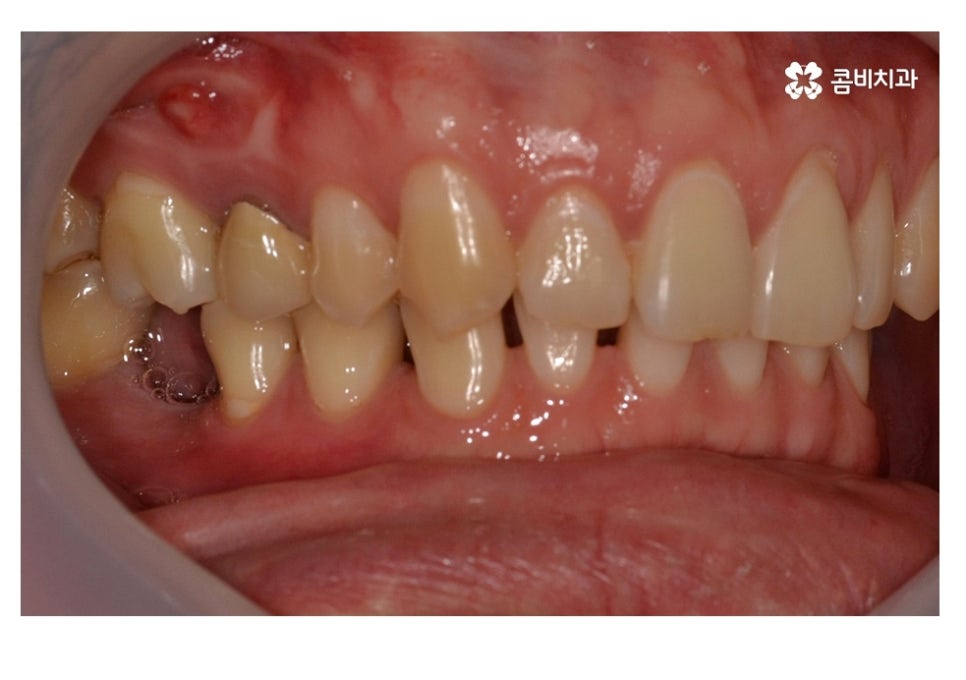

사고로 인해 치아가 깨지거나 부러지는 사례를 보면 앞니에서

주로 많이 나타나지만 충치로 심해져서 20대임플란트

시술로 이어진다거나 실수로 딱딱한 물질을 씹어서 치아가 깨지거나

금이 가는 사례를 보면 어금니에 해당하는 경우가 많이 있는데요.

저작기능에서 주된 역할을 하고 있는 부위가 어금니라는 점에서

보더라도 충치가 치아 홈에서 점점 깊어지는 사례는 물론이며

치아 사이에 음식물이 끼면서 충치가 심해지고 신경치료 및 발치로

이어지는 경우를 자주 볼 수 있는 부위라고 할 수 있어요.